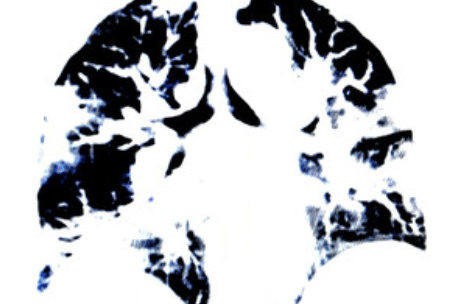

AI for Social Good: COVID-19 image analysis

Chest computerized tomography (CT) images are one of the visual medical data used in the diagnostic decision-making of COVID-19. Our artificial intelligence tool helps increase the accuracy of AI models and heightens the model training procedure.

- Our Deep U-Net technique increases the precision of the lung area detection.

- We sped up the model training process by 3600%, reducing the time needed from 72 hours to 2 hours.